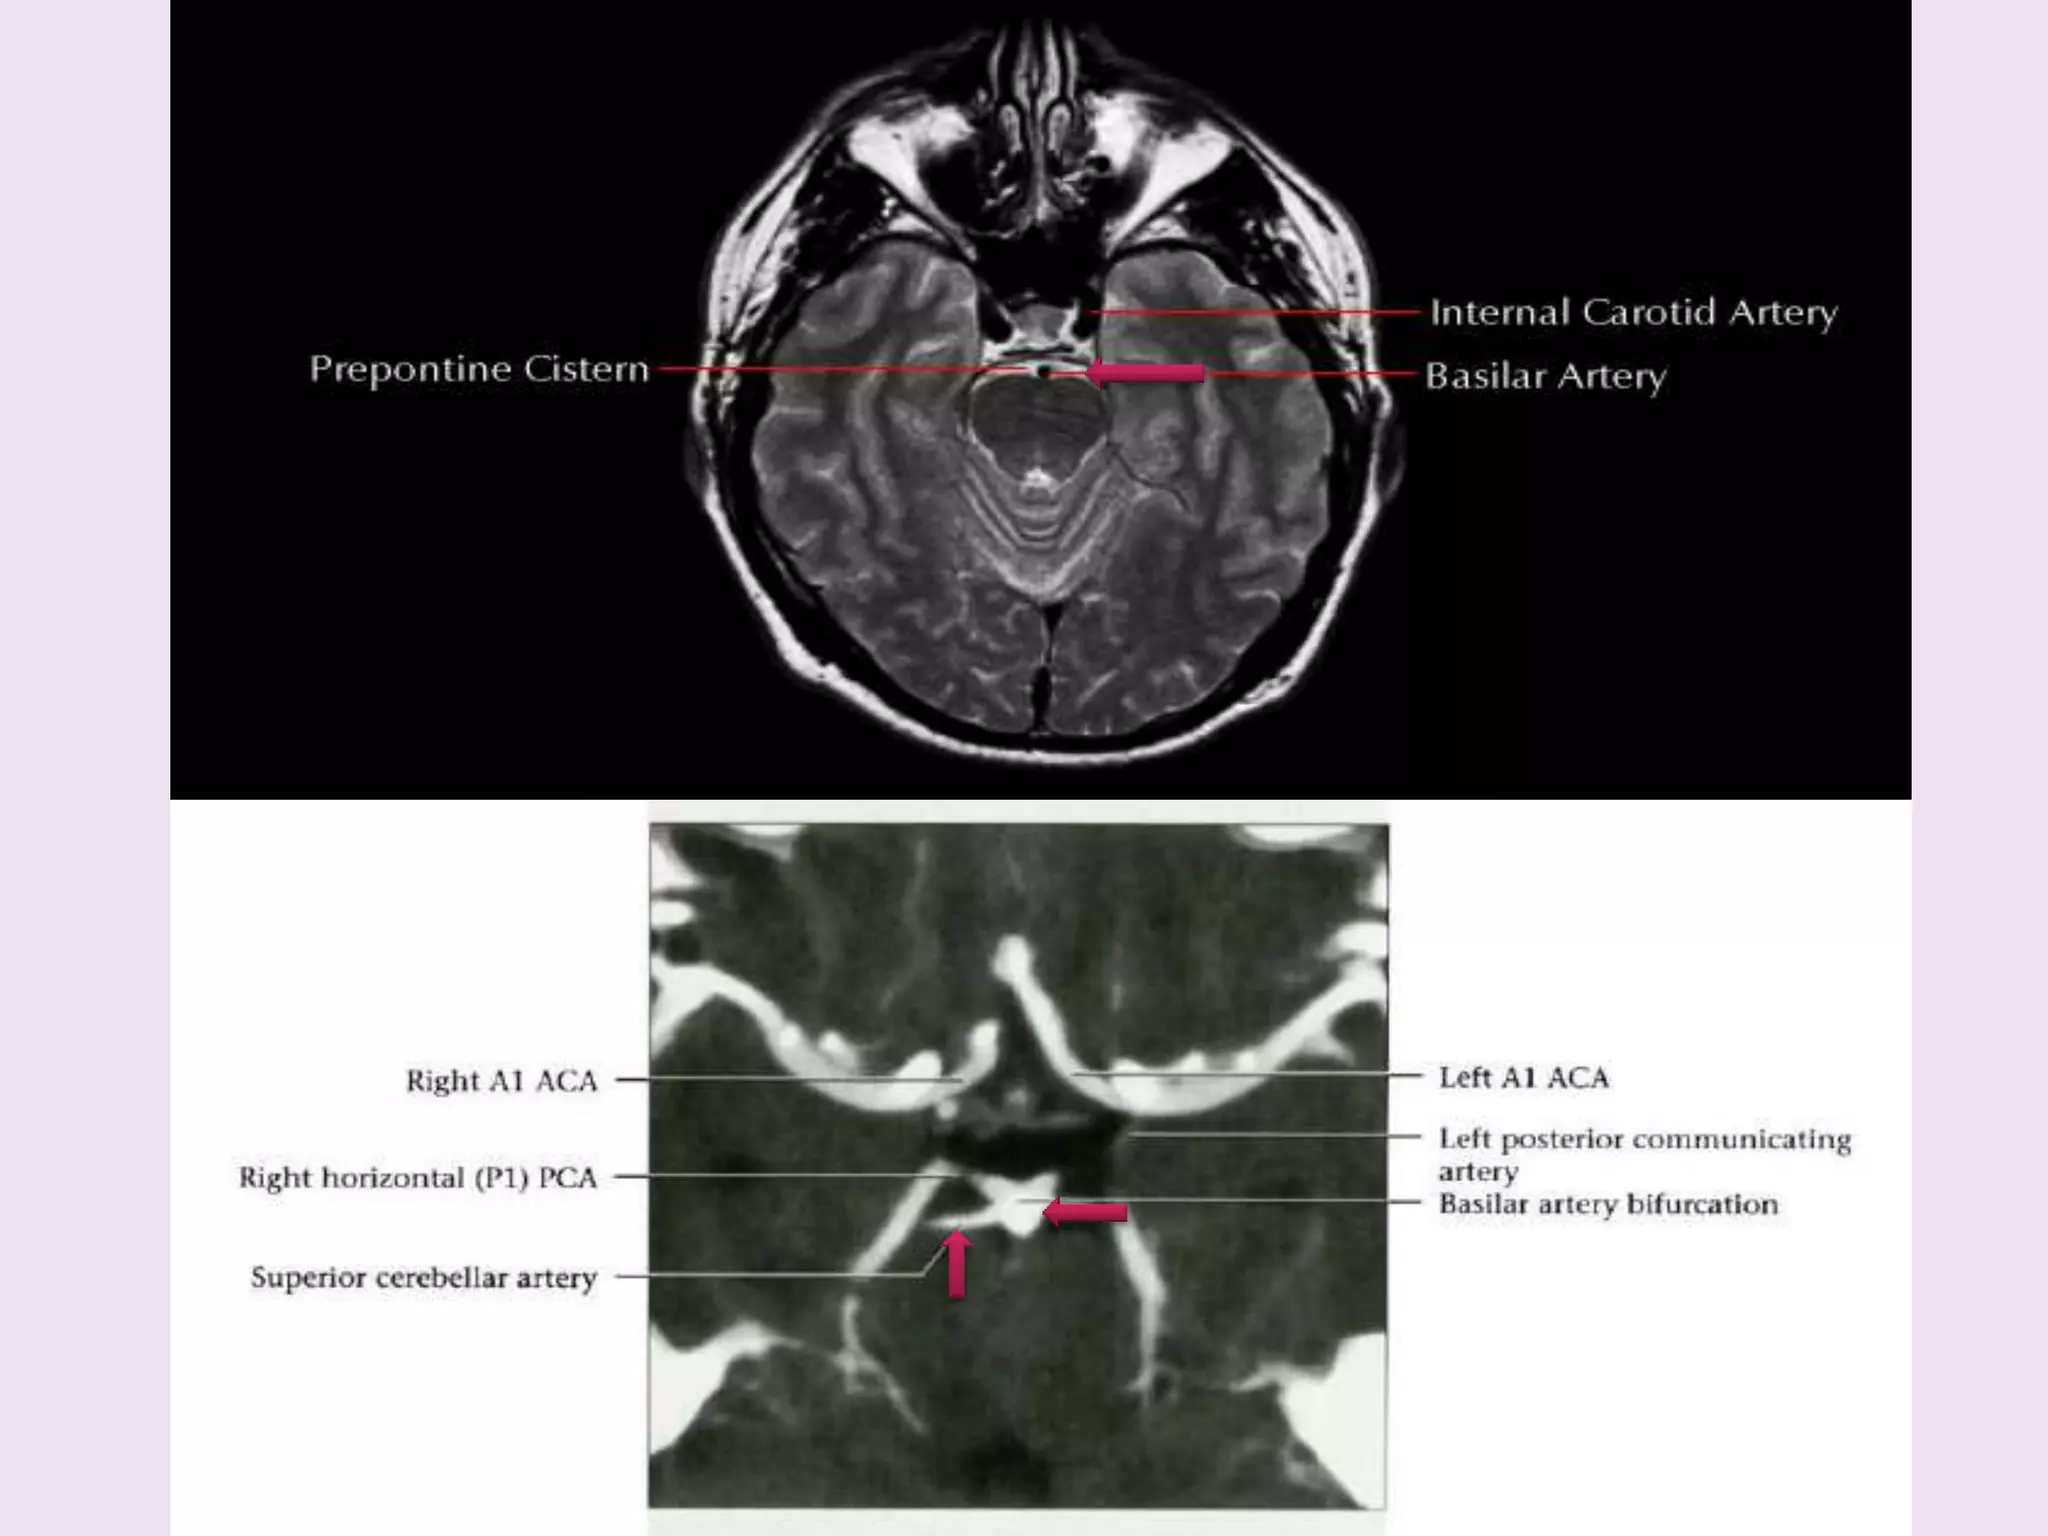

PCA origin from bifurcation of basilar artery in interpeduncular cistern.

Lies above occulomotar nerve.

P1 precommunicating /

peduncular

• Basilar bifurcation extends

laterally

• Junction with PCoA

P2 ambient / crural

Right and leftVA s unite – BA Course cephalad in front of pons Pontine cistern in the space delineated by lateral margin of clivus and dorsum sellae Terminates in interpeduncular cistern Divides into PCAs •Average length – 3 cm •Width 1.5- 4 mm •Diameter <4.5 mm